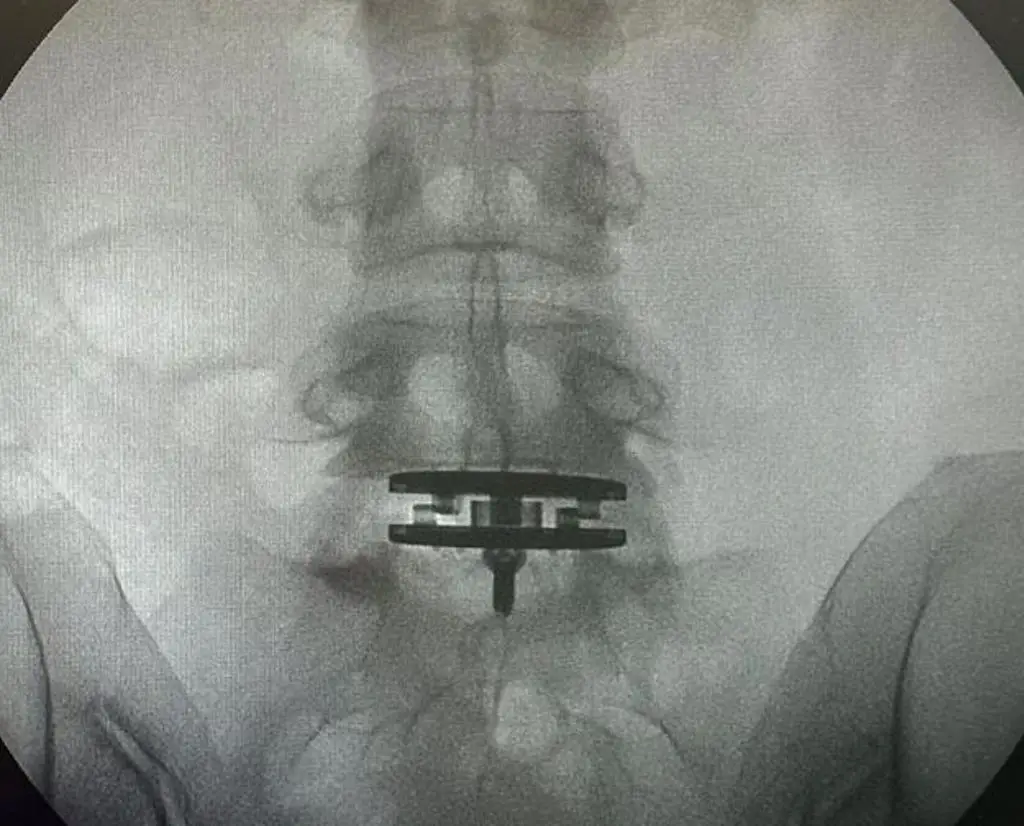

陳奕迅老婆徐濠縈2022年腰椎間盤手術(shù)后,狀態(tài)未明顯好轉(zhuǎn),打噴嚏都會(huì)引起劇痛,近日她再次接受手術(shù)。24日,徐濠縈曬出X光照片,可見腰椎接近骨盆的位置放入了儀器在治療。女兒康堤也為她打氣:“加油媽媽!”目前,手術(shù)結(jié)束,徐濠縈靜心休養(yǎng)。